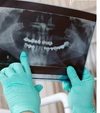

Implant tedavisi

Çene Kistleri